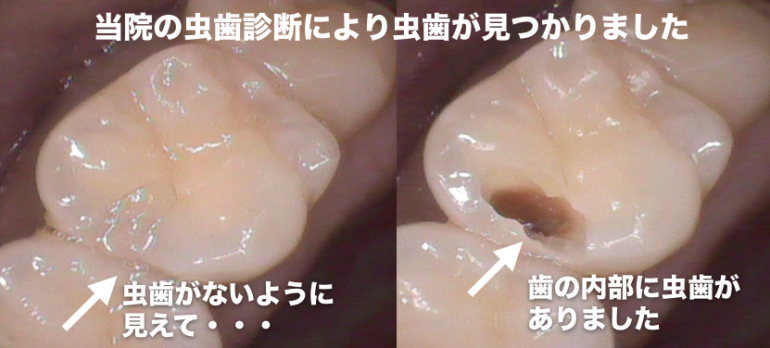

歯科医師によりレントゲンから虫歯を判断する能力(技術)には差があります

当院では、虫歯診断能力のある歯科医師が在籍しているため、適切な診断をし治療をしています

CASE1

CASE2

虫歯の治療を受ける場合は、患部の写真を撮って治療してもらえる歯科医院に行くことをオススメしています

当院では治療する場合は、口腔内写真を必ず撮影し、治療前と治療中、治療後で最低3枚以上撮影して、 治療後にどのような状態だったのか写真を撮って説明しています

問題が起きている歯や歯茎を口腔内専用カメラで撮影し治療前と治療後を比較。

治療後にモニターに映して説明しています。